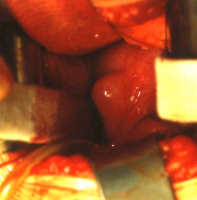

Bei dem 11 Jahre alten Mädchen mit Ureterozele und partiellem sekundärem Megaureter wurde wegen rezidivierender Harnwegsinfekte (Pyelonephritis) die Ureterozelenabtragung und Reimplantation durchgeführt und zwar mit Rücksicht auf das Lebensalter und um bei der vorgeschädigten linken Niere einen bei alleiniger Schlitzung drohenden Reflux zu verhindern (Abbildung 8).